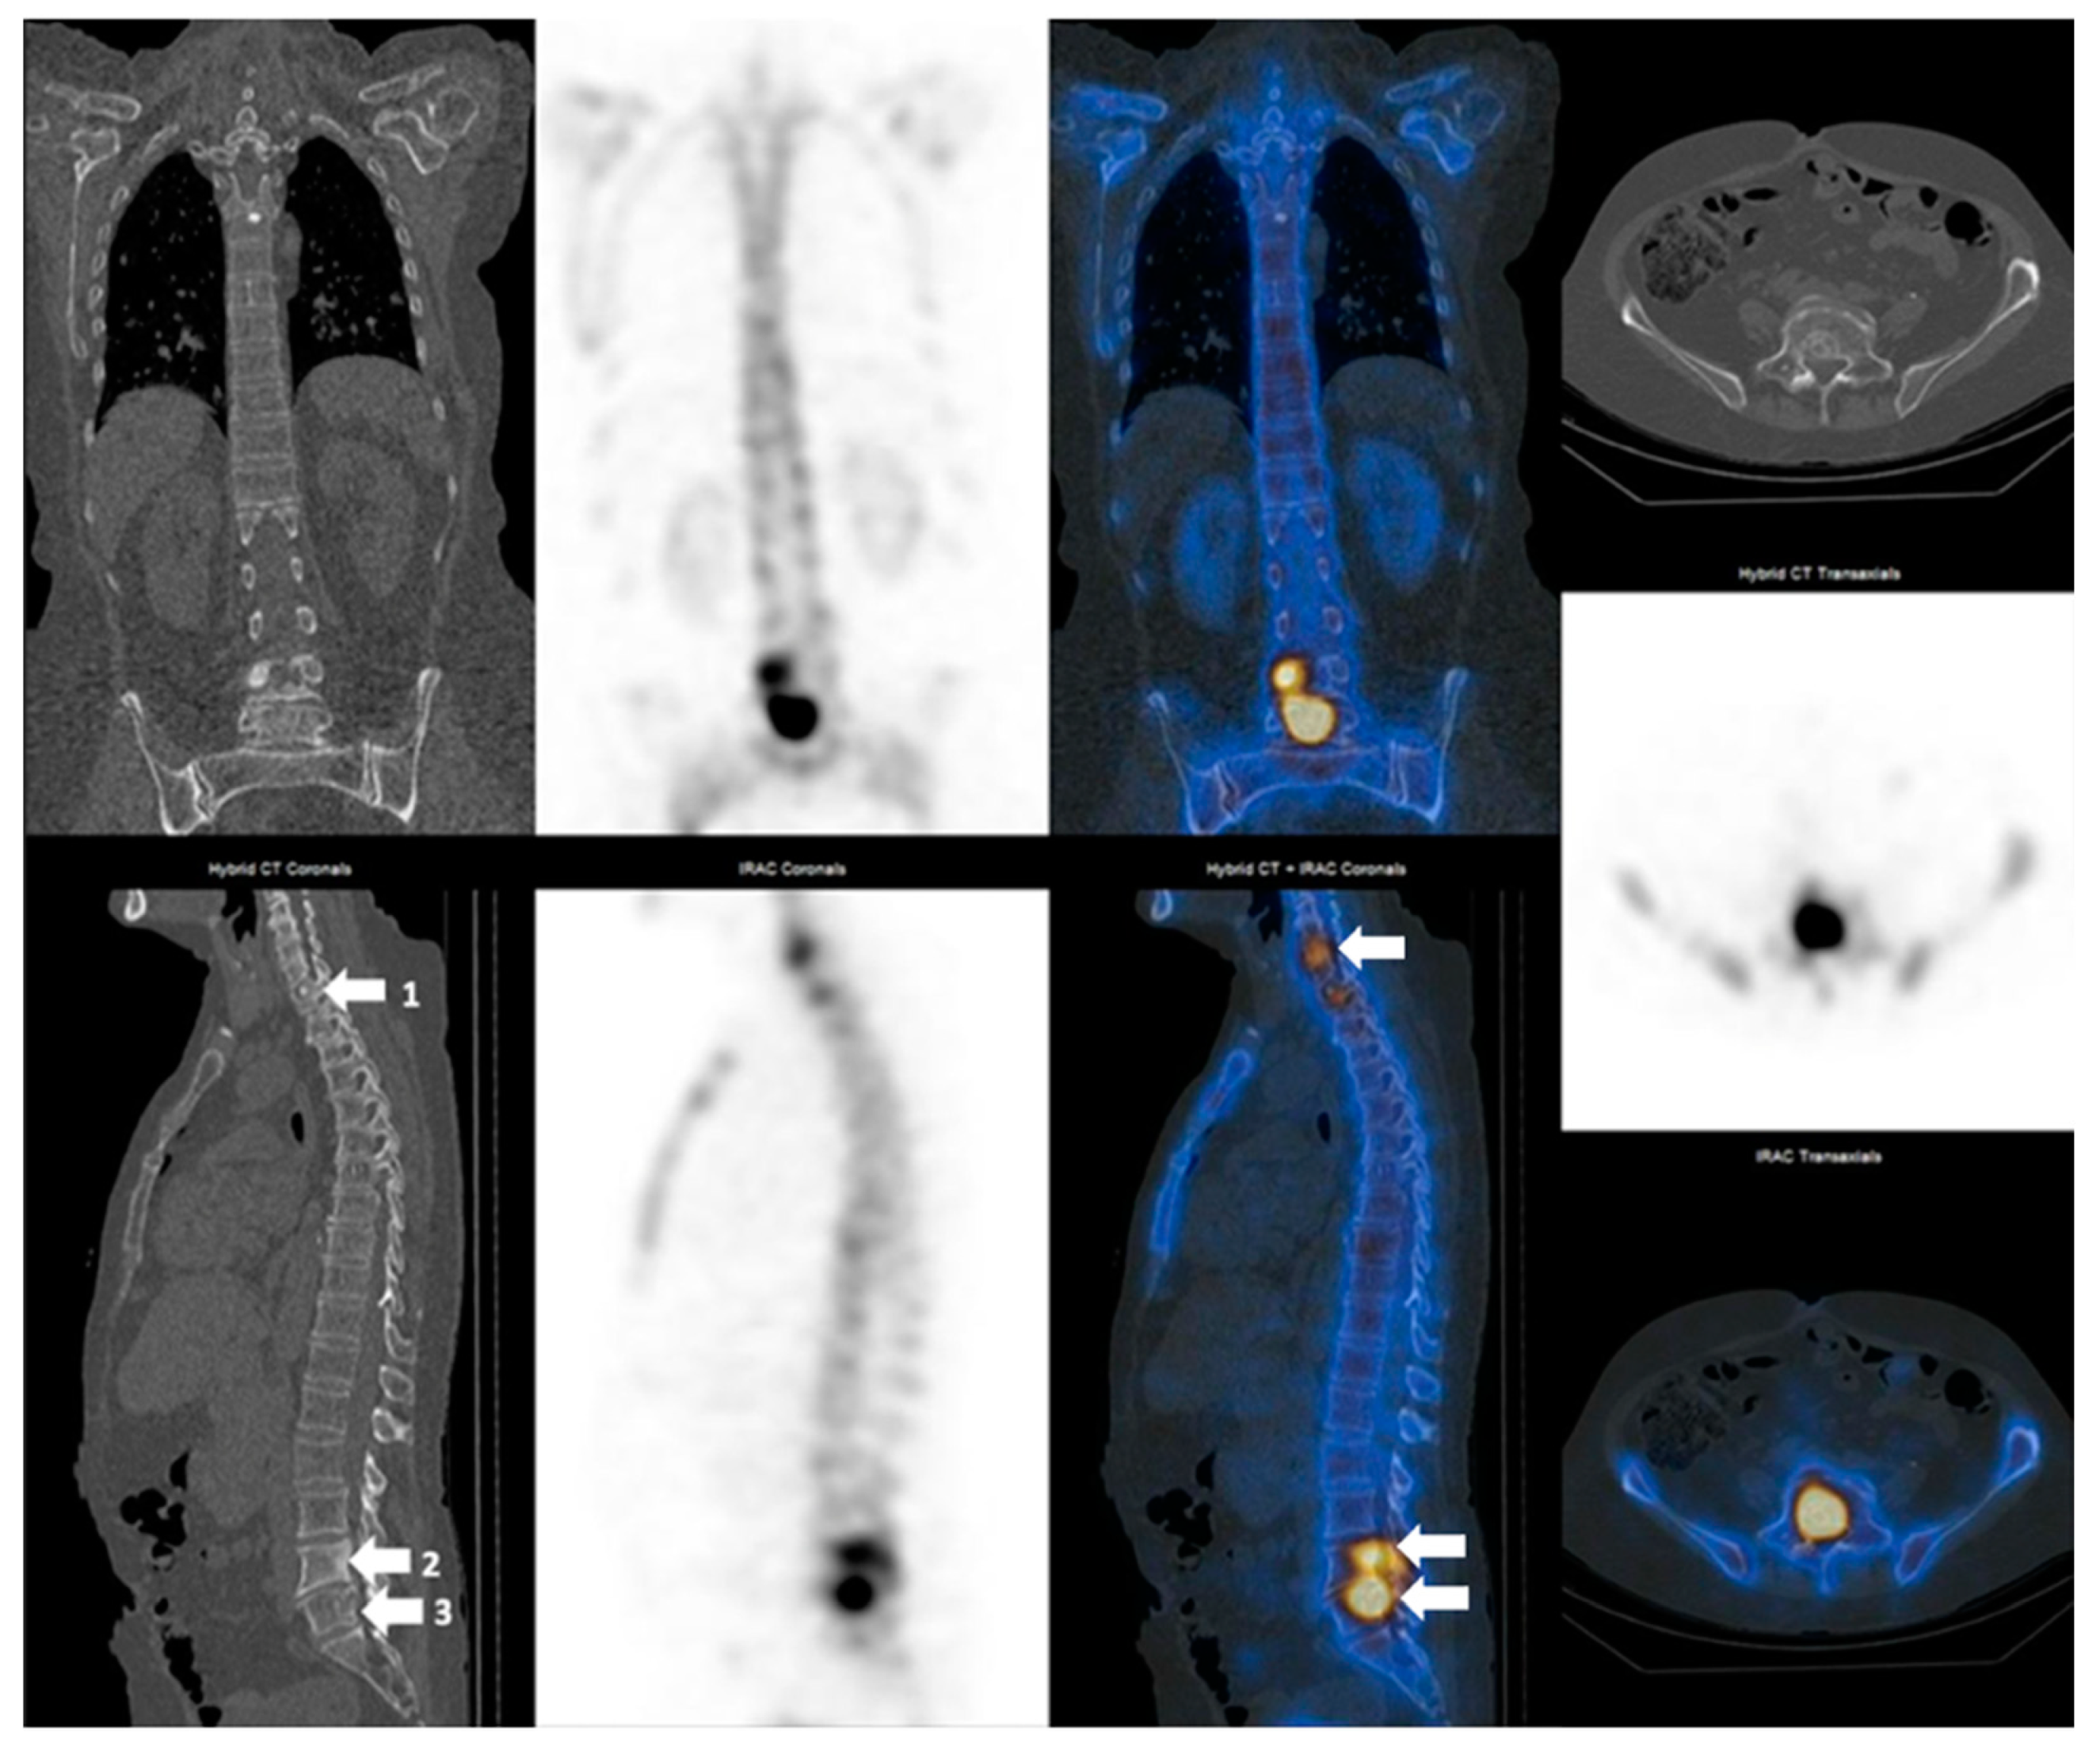

3.2. SPECT-CT SUVmax in Metastatic Lesions and Degenerative Bone Disease

3.3. SUVmax Cutt-off Value in Differentiating between Degenerative and Metastatic Lesions

3.4. SUVmax Overlapping